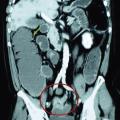

Tomodensitométrie abdomino-pelvienne (fig. 4, 5) :

• 1) Elle fait le diagnostic positif de l’occlusion (présence d’anses grêles dilatées de diamètre supérieur ou égal à 25 mm si la valvule de Bauhin est incontinente et d’une partie du côlon de diamètre supérieur ou égal à 60 mm en amont de la tumeur).

• 2) Elle détermine la topographie (colique).

• 3) Elle détermine l’étiologie : l’adénocarcinome se traduit par un épaississement dédifférencié et sténosant de la paroi digestive en virole avec parfois infiltration de la graisse adjacente et adénomégalies péritumorales.

• 4) Elle identifie des signes de gravité (perforation, pneumatose pariétale, anomalies de rehaussement des anses spécialement sur le cæcum) (fig. 5).

• 5) Elle fait un bilan d’extension (fig. 5).